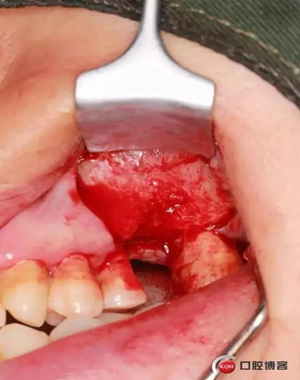

改良式外提升工具盒-外提 科貿(mào)嘉友收錄

六個(gè)月之后